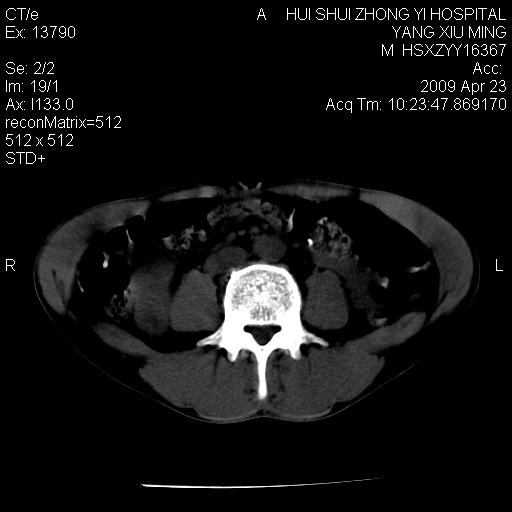

上腹部疼痛一月,呕吐10天,发现左侧颈部包快10天 胸部cr片未见明显异常。

腹膜后淋巴结增大,转移、淋巴瘤?胰腺增大,胰腺炎?占位?颈部考虑增大淋巴结。建议腹部增强扫描。

缺少强化资料,暂考虑胰腺癌广泛转移.

黑!广泛淋巴结肿大不符合胰腺癌转移。胰腺周围淋巴结肿大致使胰腺看起来大。考虑淋巴瘤可能大。

颈部及腹膜后淋巴瘤可能性大